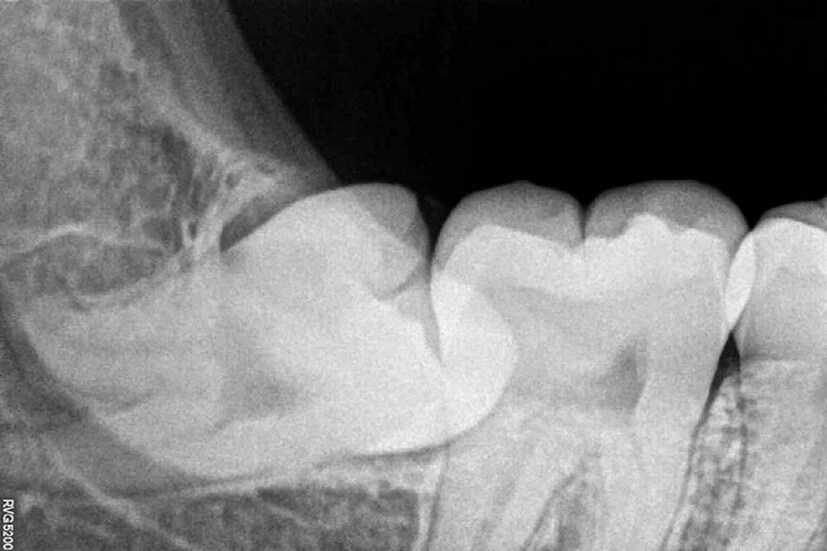

আক্কেল দাঁত কেন ওঠে? আর ওঠার সময় এত ব্যথা কেন হয়? সবার কিন্তু আক্কেল দাঁত ওঠে না, সেটাই বা কেন? আক্কেল দাঁত ওঠে কেন? এই প্রশ্ন কখনও আপনার মাথায় এসেছে? আক্কেল দাঁত এবং তার কারণে ব্যথা, চেনা মহলে এমন কথা প্রায়শই শোনা যায়। আক্কেল দাঁতের সমস্যা কি গুরুতর? দাঁতের অন্য সমস্যার সঙ্গে এর কি সম্পর্ক রয়েছে? আক্কেল দাঁত নিয়ে ভয় না থাকলেও, সজাগ না হলে সংক্রমণ হতে পারে।

তবে কি আক্কেল দাঁত তুলে ফেলাই কি সমাধান? কিছু ক্ষেত্রে এমন ভাবে আক্কেল দাঁত বেরোয় যে, গালে ঘষা লাগে। একে বলা হয় বাক্কোভার্টেড উইসডম টুথ। এ ক্ষেত্রে হয়তো সরাসরি ব্যথা হচ্ছে না। তবে আক্কেল দাঁতের কারণে মুখের ভিতরে আলসার বা ওই দাঁত সংলগ্ন টিসুতে সমস্যা তৈরি হয়। তখন দাঁত তুলে ফেলা সমীচীন। আক্কেল দাঁত তির্যক ভাবে বেরোলে, দাঁতের ফাঁকে খাবার আটকে যেতে পারে। এতে আক্কেল দাঁত ও তার পাশের দাঁতে ক্যাভিটি হতে পারে। আক্কেল দাঁতের যে কোনও সমস্যায় অবশ্যই চিকিৎসকের পরামর্শ নেওয়া জরুরি। (Disclaimer: এই প্রতিবেদনটি কেবলমাত্র সাধারণ তথ্যের জন্য, তাই বিস্তারিত জানতে হলে সর্বদা বিশেষজ্ঞের পরামর্শ নিন।)